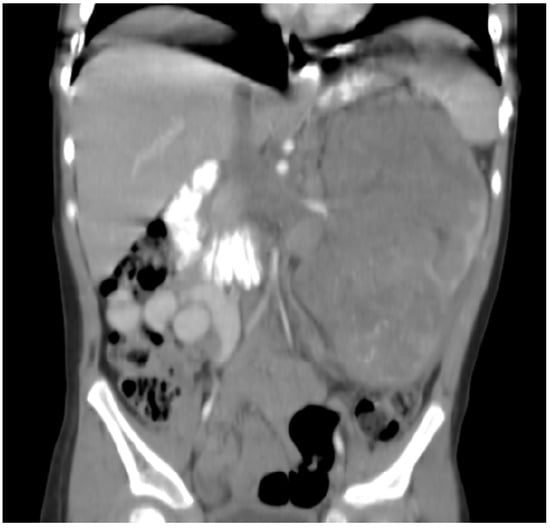

This patient was a Hispanic boy diagnosed with metastatic neuroblastoma when he presented with an 8 × 12 cm right suprarenal mass, extensive retroperitoneal and mesenteric lymphadenopathy, spinal cord compression, and metastatic bone disease to the right scapula and body of L1 at 9 years of age. He was treated with high-dose cisplatin and etoposide, cyclophosphamide, Adriamycin and vincristine, ifosfamide and etoposide, and carboplatin and etoposide, followed by subtotal resection of the retroperitoneal tumor and right kidney as per ANBL00P1 [38]. PBSCT was not available due to a lack of funds, for which he received two cycles of topotecan–cyclophosphamide, followed by 2160 cGy radiation to the tumor bed and spine, followed by 6 months of isotretinoin. He had no evidence of residual disease at the end of treatment. Seven months later, he developed recurrent neuroblastoma involving the right external iliac lymph nodes, for which he started palliative metronomic chemotherapy with oral VP16 (50 mg/m2/day; days 1–21) alternating with oral CTX (75 mg/m2/day; days 22–41) and continuous sulindac (4 mg/kg/day). He had hematologic toxicity requiring interruptions and dose reductions of both VP16 and CTX. Evaluation showed decreased tumor size at 5 and 8 months of therapy. He subsequently developed progressive disease after 11 months on therapy, for which sulindac was changed to celecoxib (500 mg/m2/day). Two months later while off prophylactic antacids, the patient developed hemorrhagic gastritis, hematemesis, aspiration pneumonia, acute renal failure, and seizures, and died 13 months after starting metronomic chemotherapy.

1.6. Patient 6

This patient is a Hispanic girl found to have a large cervicomedullary tumor with a cervico-thoracic central syrinx with tumor seeding when she presented with right shoulder drop and right upper-extremity weakness at 3 years of age (Figure 4A). She had resection of the cervicomedullary portion of the tumor. Evaluation revealed a type 2 neurocytoma of the spine.

Patient 6: (A) MRI shows a 4.5 cm homogeneously enhancing expansile intramedullary tumor involving the medulla and upper cervical cord down to the level of C3–C4 (arrow) with an elongated syrinx extending inferiorly to the T3–T4 level; (B) the tumor was removed and treated with radiation but came back, for which it was treated with nine cycles of topotecan–ifosfamide–carboplatin with no significant change in tumor size (arrow) but significant toxicity, for which treatment was changed to metronomic chemotherapy; (C) after 3 months on metronomic chemotherapy, the patient recovered from toxicity and the tumor was slightly decreased; (D) the tumor was stable at the end of 4 years of metronomic chemotherapy.

She subsequently received intensity-modulated radiotherapy to the tumor bed and residual cervico-thoracic tumor. Following radiation, a residual 11 mm expansile cervicomedullary nodule, centered at the C3–C4 level, was documented. Five months later, she developed progressive disease with increased size of the cervicomedullary nodule to 15 mm and development of a new second focus of enhancement on the ventral aspect of the spinal cord at C2. She was treated with topotecan, ifosfamide and carboplatin (TIP). She had significant hematologic toxicity and infectious complications during this treatment and no change in tumor size after nine cycles (Figure 4B), for which she was changed to metronomic chemotherapy with 21 days of temozolomide (60 mg/m2 day) aleternating with 21 days of CTX (50 mg/m2), VA (15 mg/kg), celecoxib (250 mg/m2/day) and bevacizumab (5 mg/kg IV every 3 weeks). Tumor response was noted 3 months after treatment with decreased tumor size to 9–10 mm (Figure 4C). Tumor size remained stable on subsequent studies, and temozolomide and CTX were stopped at 18 months, celecoxib and VA were stopped at 36 months, and bevacizumab was stopped at 48 months (Figure 4D). Metronomic chemotherapy was restarted after tumor progression was documented 10 months later (Table 1). She developed stable disease and treatment was stopped 15 months later. She remains with stable disease 4 years off therapy.